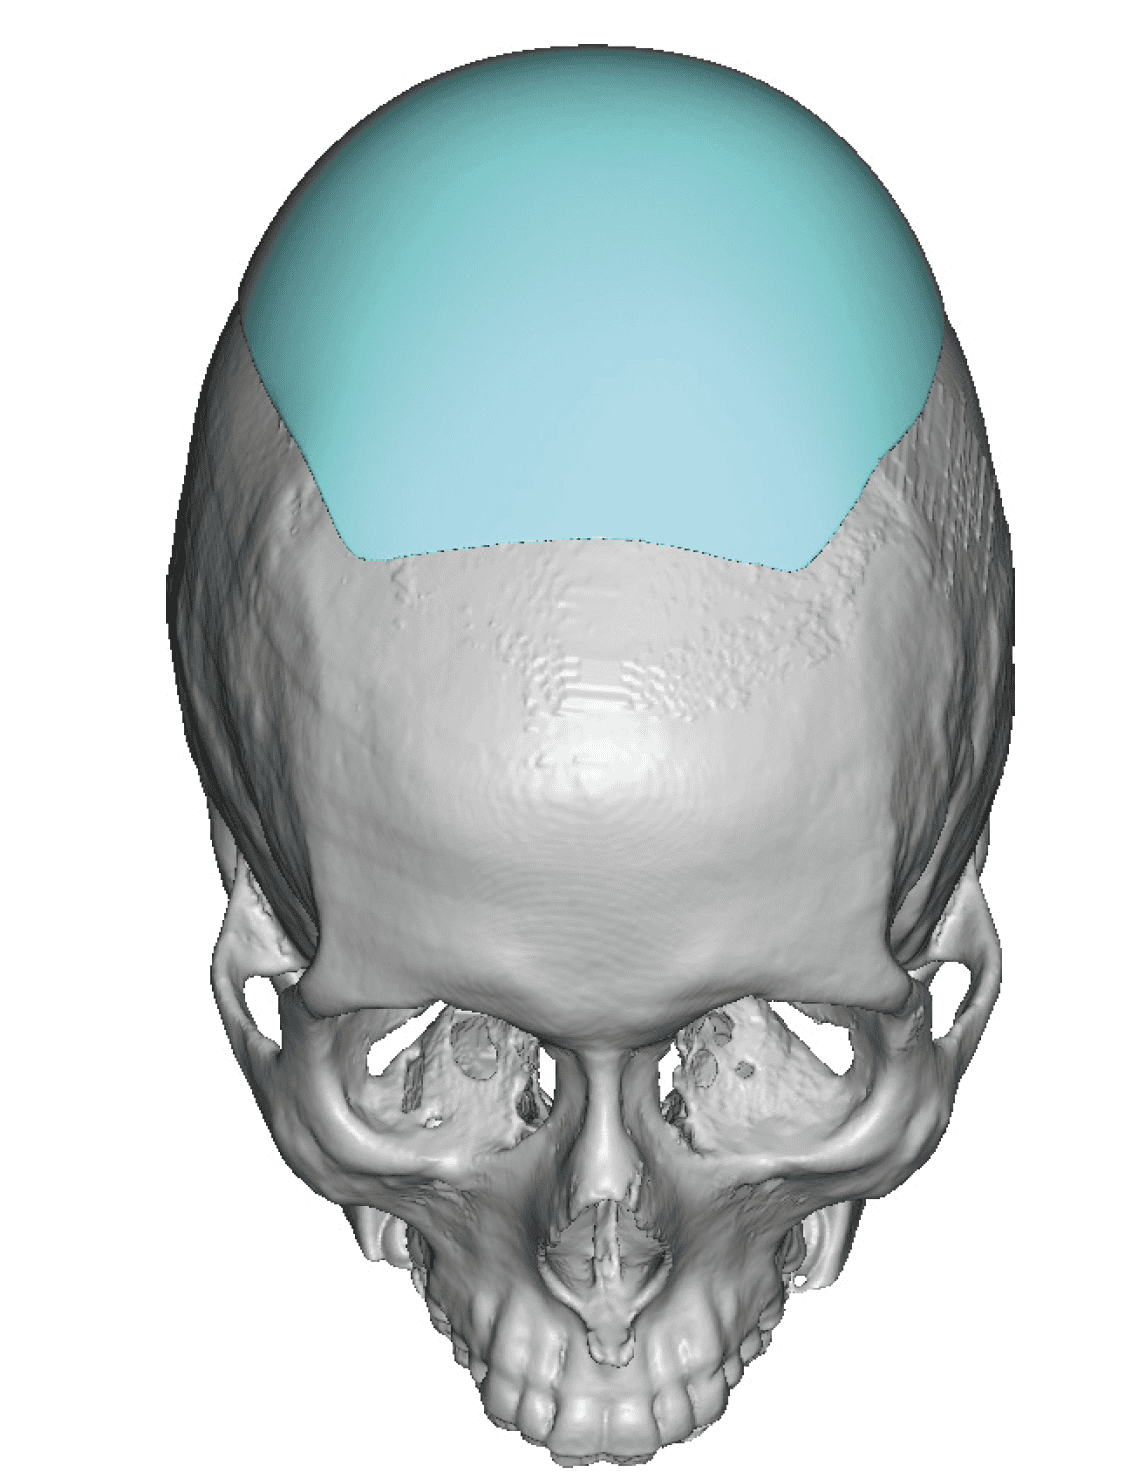

Patient 49

Desire for further skull augmentation after a primary skull implant.

Five years after an initial custom skull implant placement a new custom skull implant that increased the volume by 35% was placed.

Desire for further skull augmentation after a primary skull implant.

Five years after an initial custom skull implant placement a new custom skull implant that increased the volume by 35% was placed.